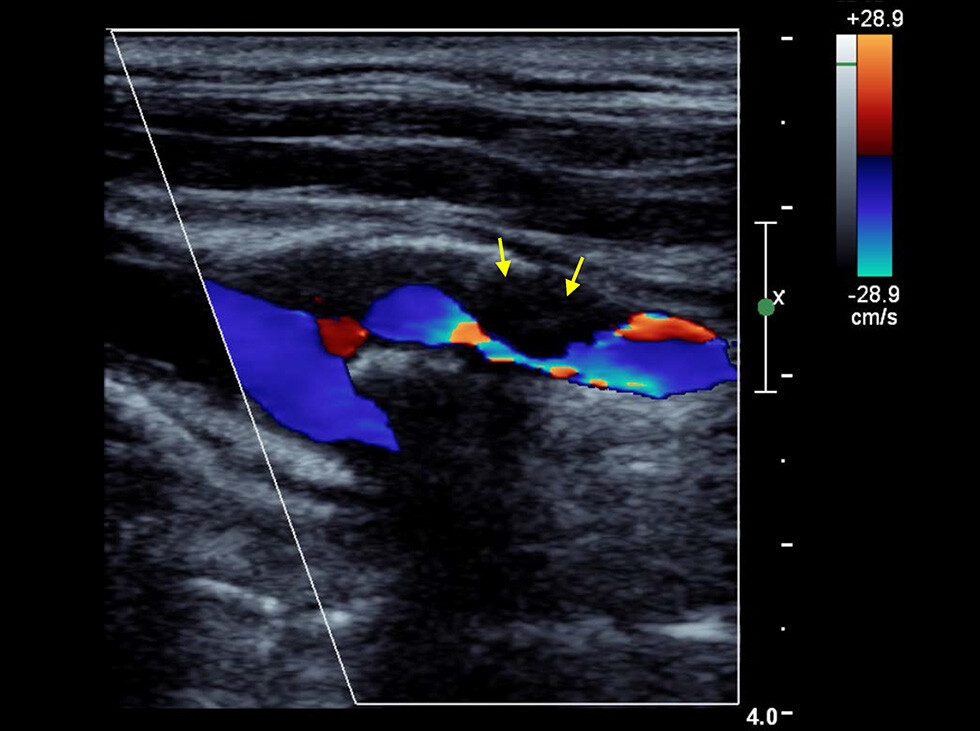

In dieser Farbduplex-Sonographie der Halsschlagader zeigen die Pfeile eine hochgradige Verengung der inneren Halsschlagader (Carotis-Stenose). © M. Reinhard, Klinik für Neurologie und Neurophysiologie, Universitätsklinikum Freiburg